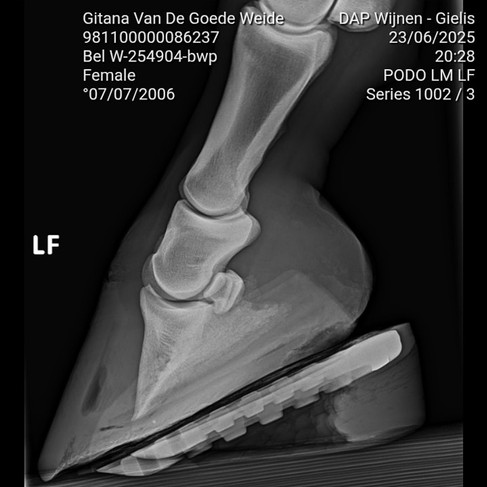

I have used Glushu on many complex cases and knew this would be a good solution. Here you can see a GluShu application with 12 degree wedge for the deep digital flexor tendon to be relieved. In addition I also employed a wedge during the shredding to get the hoof bone back into a good angle. To complete the job I filled the shoe with Shupack CS to provide counter-pressure.

The X-rays show before and after.